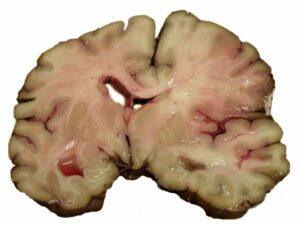

Intracerebral hemorrhage.

- Intracerebral_hemorrhage © Yadav YR, Mukerji G, Shenoy R, Basoor A, Jain G, Nelson A is licensed under a CC BY (Attribution) license